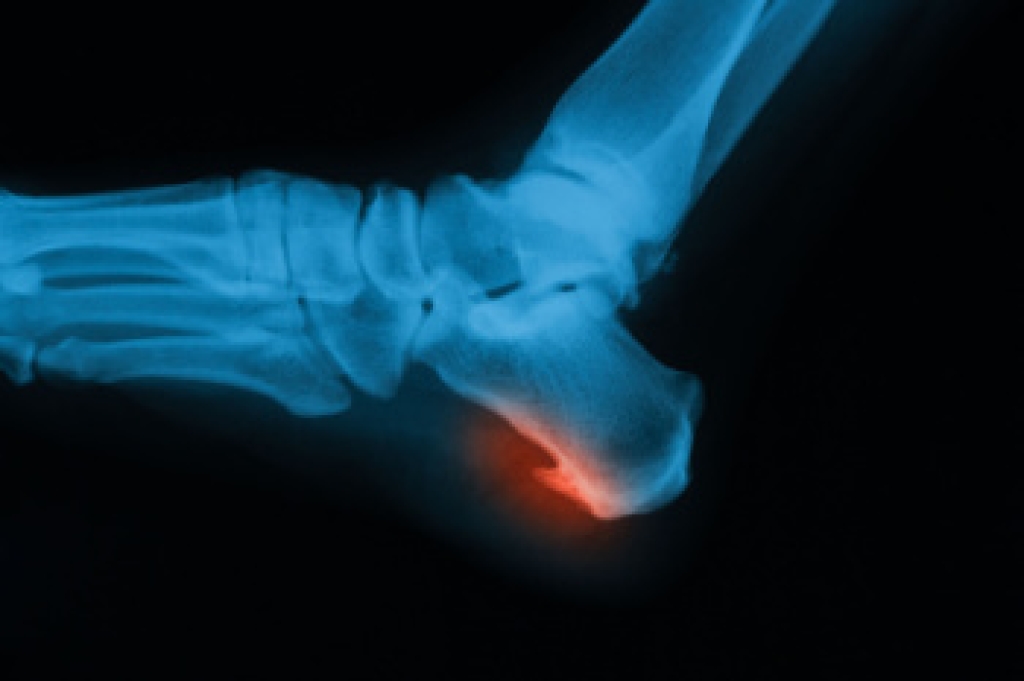

Toenail removal is sometimes necessary when severe injury, chronic ingrown growth, or infection damages the nail and surrounding tissue. An ingrown toenail occurs when the nail edge presses into the skin, leading to inflammation, drainage, and discomfort that worsens with pressure or while wearing tight shoes. If an infection develops or the nail repeatedly grows into the skin, removal may be needed to prevent further tissue damage. A podiatrist can determine whether partial or complete toenail removal is appropriate. In some cases, the nail matrix, which is the tissue that produces nail growth, is treated to prevent recurrence. This procedure is typically performed under local anesthesia, allowing the podiatrist to remove the affected section and safely clean the area. If you have a seriously infected toenail, it is suggested that you promptly schedule an appointment with a podiatrist who can offer effective treatment and relief solutions, which may include minor surgery.

Foot surgery is sometimes necessary to treat a foot ailment. To learn more, contact Adriana Strimbu, DPM of Complete Foot & Ankle Care. Our doctor will assist you with all of your foot and ankle needs.

When Is Surgery Necessary?

Foot and ankle surgery is generally reserved for cases in which less invasive, conservative procedures have failed to alleviate the problem. Some of the cases in which surgery may be necessary include:

What Types of Surgery Are There?

The type of surgery you receive will depend on the nature of the problem you have. Some of the possible surgeries include:

Benefits of Surgery

Although surgery is usually a last resort, it can provide more complete pain relief compared to non-surgical methods and may allow you to finally resume full activity.

Surgical techniques have also become increasingly sophisticated. Techniques like endoscopic surgery allow for smaller incisions and faster recovery times.